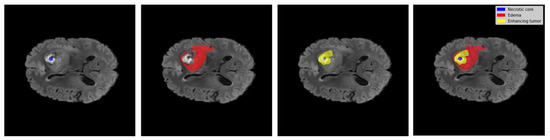

2.2. Characterizing Tumor Sub-Regions for Segmentation Task

In this study, the segmentation task of the BraTS data involves the accurate identification and classification of three distinct components as in Figure 3 within brain tumors, using sophisticated image processing and machine learning techniques. The following outlines the specific sub-regions of the brain tumor:

Figure 3. Tumor regions: 1. necrotic core 2. edema 3. enhancing tumor.

Enhancing tumor: This term refers to the portion of the tumor that displays increased intensity on contrast-enhanced MRI scans, highlighting the active and aggressive parts of the tumor. The presence of an enhancing tumor, which indicates a disruption in the blood–brain barrier that allows contrast agents to leak into the tumor tissue, is crucial for evaluating the tumor’s aggressiveness and pinpointing the primary focus for therapeutic interventions. It reflects areas where the tumor is most likely to grow and spread, making it a focal point for surgical and medical treatments [17,18].

Edema: In the realm of brain tumors, edema signifies the swelling or accumulation of fluid in the brain tissues surrounding the tumor, visible on MRI scans as areas of hyperintensity on T2-weighted images. Edema is a vital indicator of the tumor’s impact on adjacent brain tissue, significantly affecting a patient’s symptoms and overall condition. Accurately identifying edema is essential for assessing the tumor’s extent and its implications on brain function, as it can influence decisions regarding the urgency and type of treatment required [18,19].

Necrosis: Necrosis within a tumor refers to areas of dead or dying cells that no longer function due to the tumor’s growth outstripping its blood supply. On MRI scans, necrosis is typically seen as a non-enhancing core within the tumor, surrounded by the enhancing tumor margin. Identifying necrosis is important for determining the stage of the tumor and its responsiveness to treatment. It also plays a critical role in surgical planning, as these areas can affect the approach to tumor resection and the prediction of treatment outcomes [18,20].

As demonstrated in Table 6 and Table 7, the Spectral–Spatial GNN method outshines both Spatial GNN and Spectral GNN across validation and test sets for tumor sub-region segmentation, achieving superior Dice Scores and accuracy for necrotic core, enhancing tumor, and edema. This method’s integrated approach, combining spectral and spatial graph analyses, allows for a nuanced representation of tumor structures, evident in its robust performance metrics; while Spatial GNN effectively utilizes local connectivity and Spectral GNN focuses on global patterns, they fall short in capturing the comprehensive tumor landscape as effectively as the Spectral–Spatial GNN. This model’s ability to accurately segment complex tumor regions, maintaining high performance across different datasets, underscores its potential as a reliable tool in medical imaging segmentation. The consistency in outperforming other methods across both datasets not only highlights the effectiveness of the Spectral–Spatial approach but also marks a significant step forward in the field, suggesting further exploration into combining modalities and advanced graph theories could yield even greater advancements in tumor segmentation. In Figure 7, the precision of the Spectral–Spatial GNN model is exemplified. The depicted brain MRI slice, extracted from the BraTS dataset showcases the predicted tumor area, illustrated with heightened clarity and precision.

Figure 7. Ground truth versus three predicted classes.